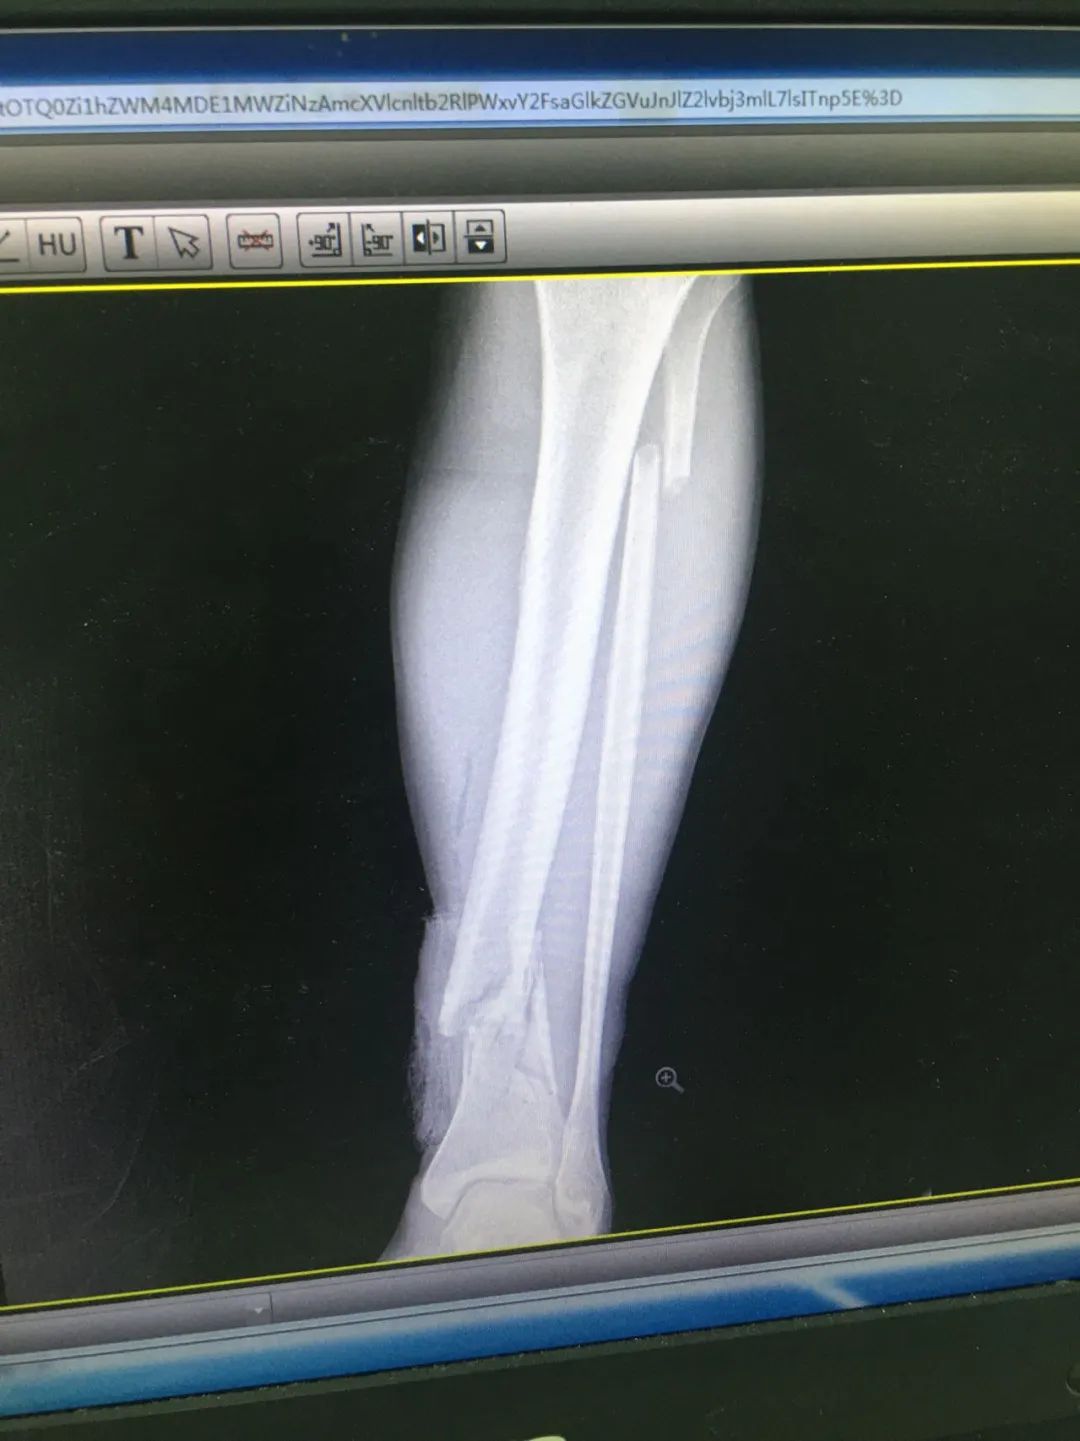

入院時(shí),劉先生已失血性休克。急診科為劉先生安排X線及CT攝片檢查,顯示左股骨干、左腓骨上端骨折,左脛骨遠(yuǎn)端粉碎性骨折,頭皮及全身多處皮膚軟組織挫裂傷,隨后收治于骨科。

第1次手術(shù)10天后,骨科為劉先生安排了第2次手術(shù),歷經(jīng)3個(gè)小時(shí),成功完成左股骨干骨折及左脛骨遠(yuǎn)端骨折閉合復(fù)位內(nèi)固定術(shù),植入兩根30cm×10mm、34cm×10mm髓內(nèi)釘。

術(shù)后一周,患者手術(shù)切口愈合良好,左下肢皮膚感覺(jué)及肌力正常,左足末梢循環(huán)恢復(fù),復(fù)查X片顯示骨折復(fù)位標(biāo)準(zhǔn),內(nèi)固定物位置良好。